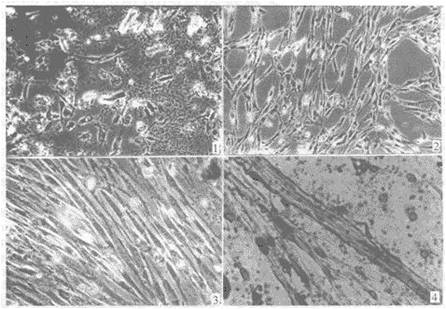

光鏡下的間充質(zhì)干細胞 電鏡下的間充質(zhì)干細胞

肌肉衛(wèi)星細胞 熒光染色的肌肉衛(wèi)星細胞

熒光染色的肝卵圓細胞